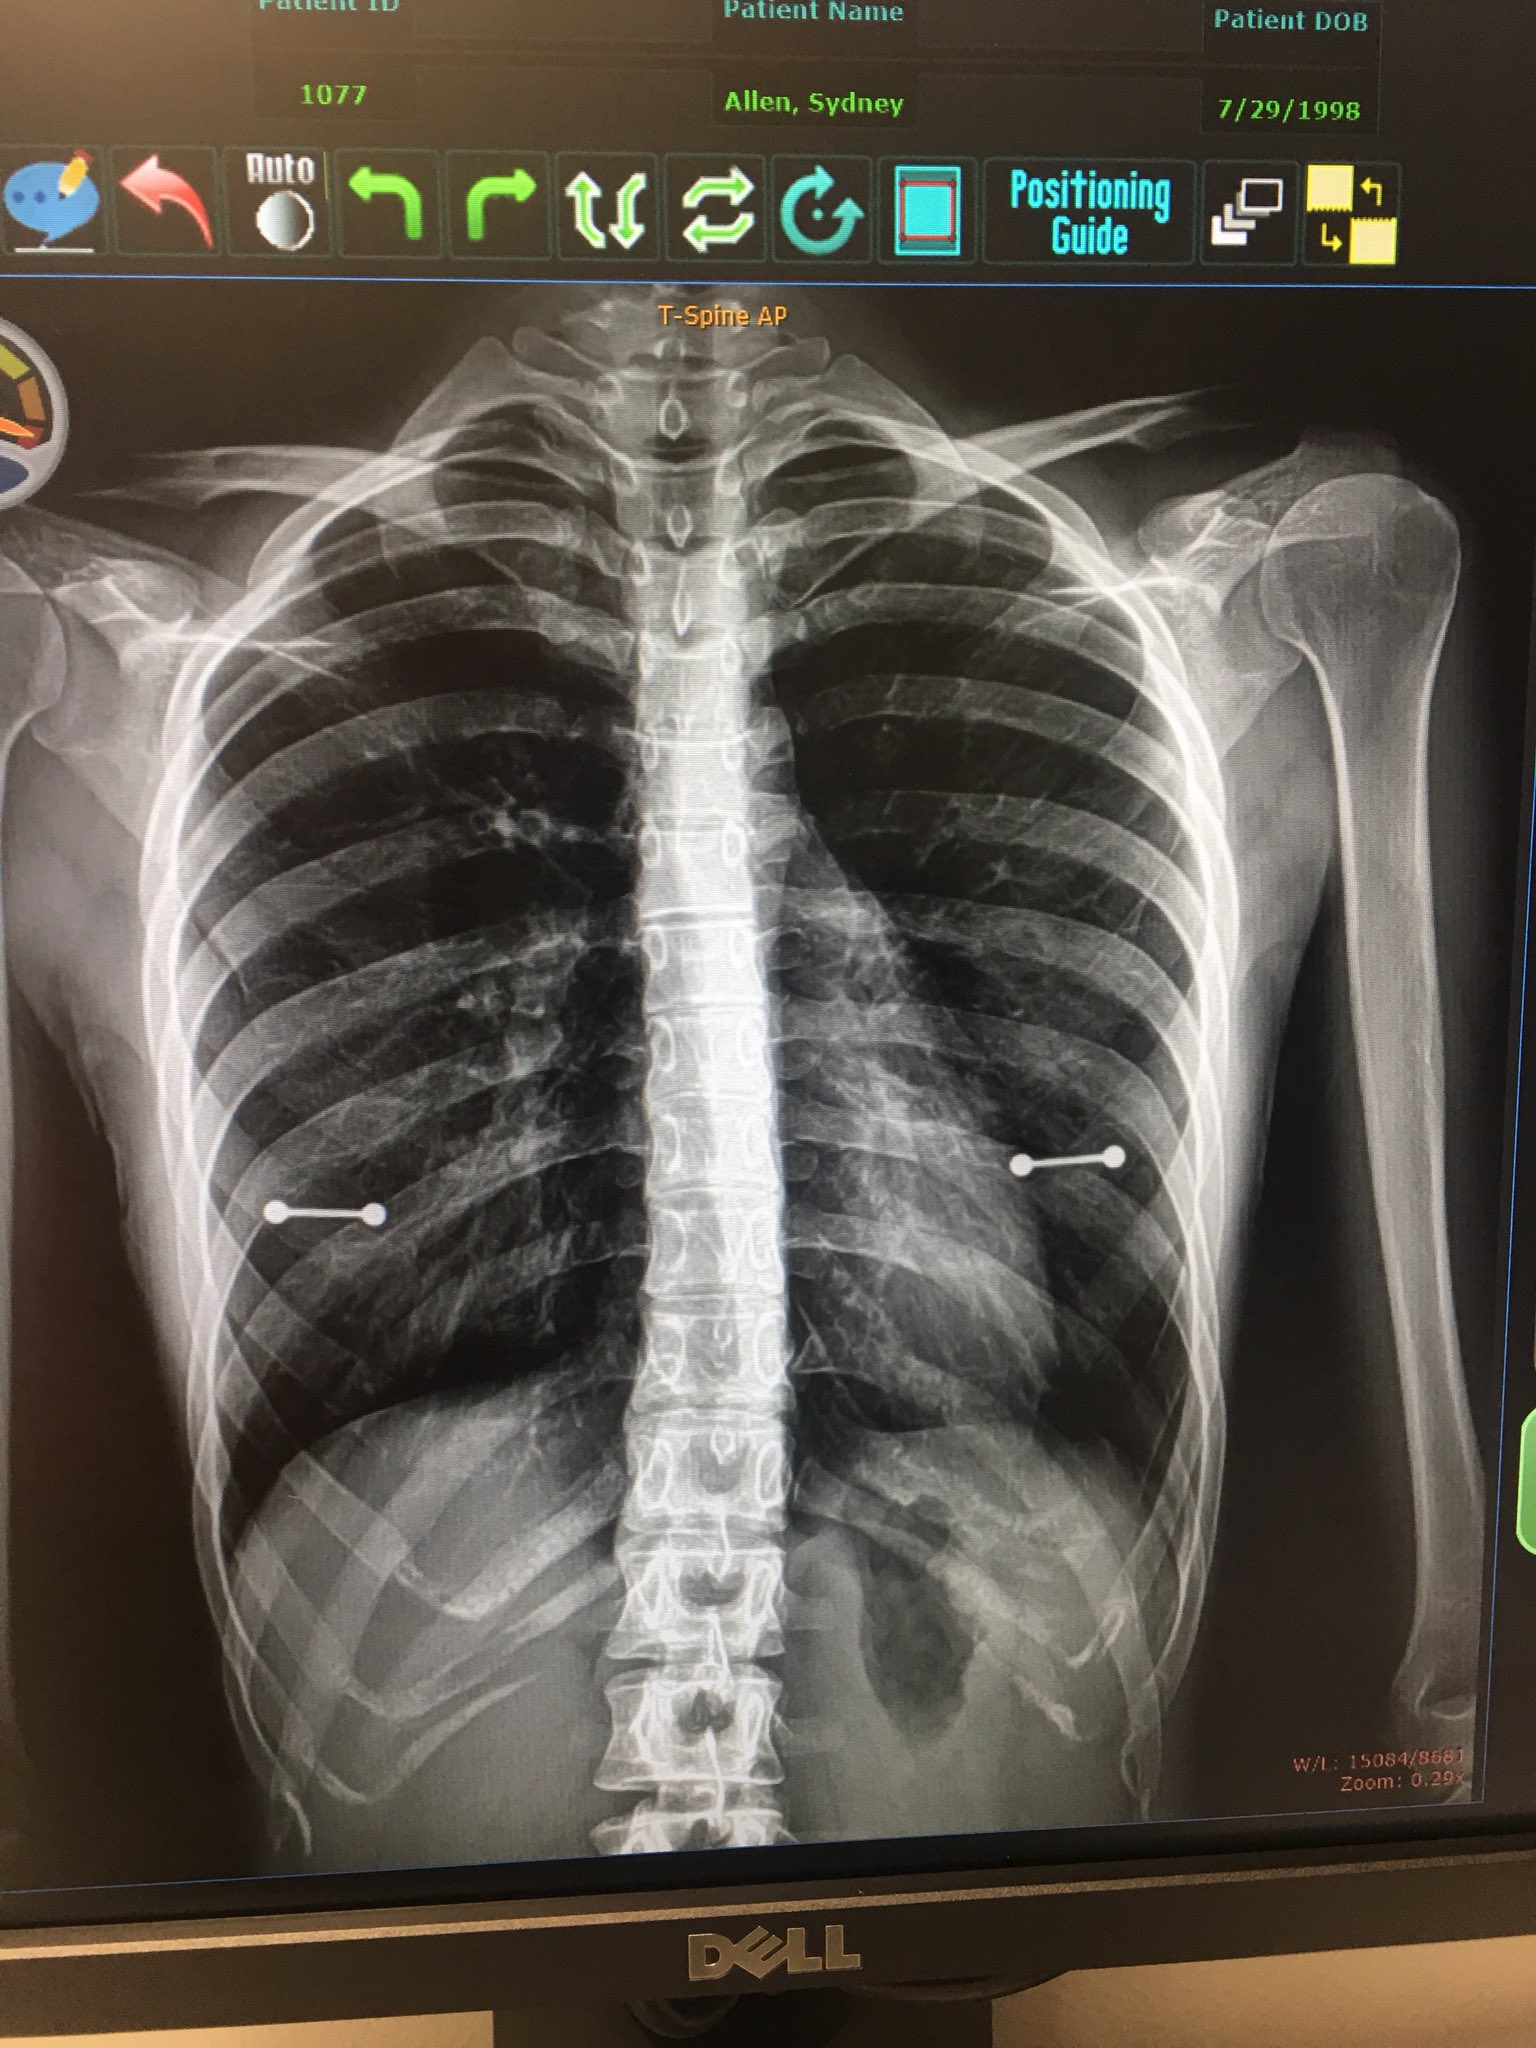

La adolescente estadounidense Sydney Allen fue a la consulta del médico para realizarse unas pruebas rutinarias pero el médico descubrió, para sorpresa de su madre, que llevaba piercings en los pezones. Todo iba bien pero los resultados de una radiografía se proyectaron y la madre descubrió "dos extrañas manchas metálicas" que se situaban en el punto exacto de los pezones de su joven hija.

Al revelarse los piercings en la radiografía (eran dos barras metálicas, tal y como mostró Sydney Allen en Twitter) la madre sufrió una gran crisis nerviosa (al estar en el hospital, pudo recibir atención médica de forma rápida) mientras que a la adolescente le entró una risa nerviosa, que acabó en un ataque de tos. El médico asistió impertérrito al espectáculo aunque no todos los días en la consulta de los rayos X se viven escenas familiares tan dramáticas que bien pueden ser el argumento de una telenovela como que una madre se entere de que su joven hija lleva sendos piercings en los dos pezones.